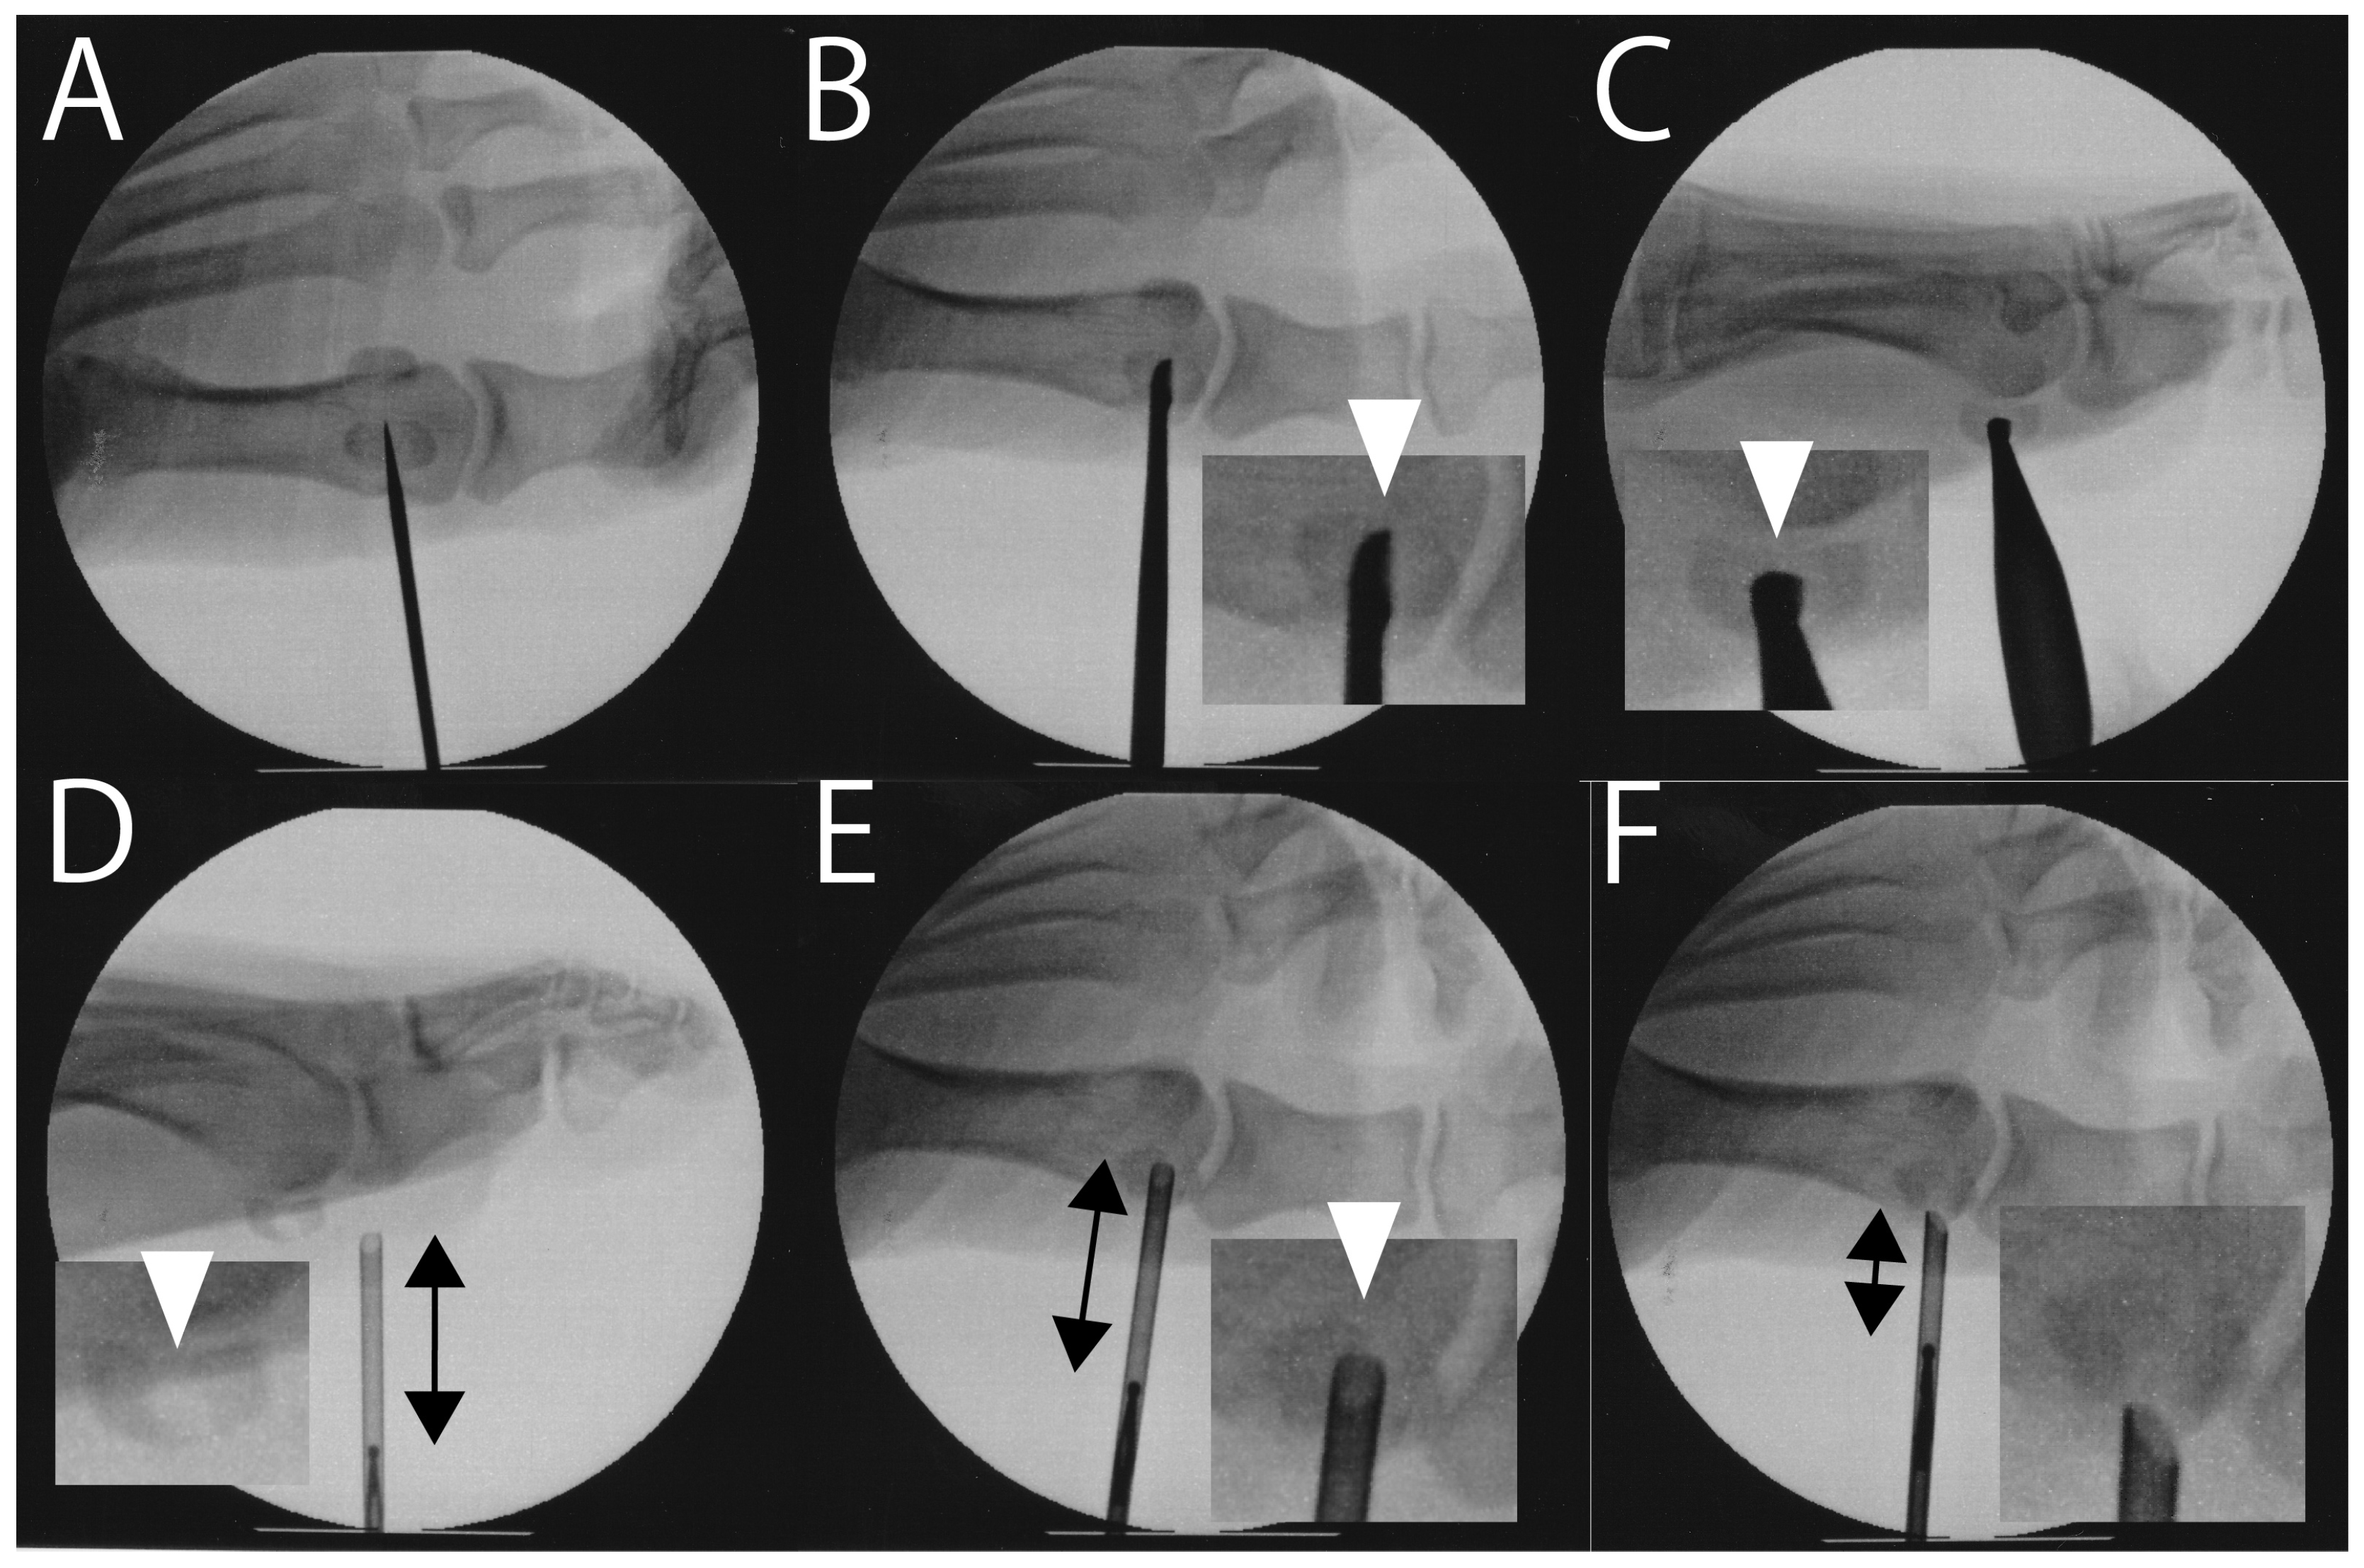

- Nakajima, K. Arthroscopic autologous bone grafting for hallux sesamoid fracture nonunion results in a high rate of complete resolution. Arthrosc. Sports. Med. Rehabil. 1789, 4, e1789–e1797. [Google Scholar] [CrossRef]

| Nakajima (2022) [73] | Case series 11 (10 tibial, 1 fibular) | Arthroscopic bone grafting | VAS 72.0 → 12.0 VAS of 0 and JSSF of 100 observed in 9/11 | Persistent pain (2/11) |